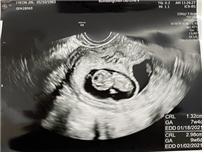

오후까진 정말 행복했다. 아이의 모습이 담긴 초음파 사진에 흥분을 감추지 못했다. 동영상 파일을 전해 받곤 ‘일시정지’와 ‘재생’ 버튼은 연신 눌러대며 스크린숏을 찍어댔다. 양 손과 발, 손가락과 발가락을 보며 눈이 휘둥그레졌고. 눈코 입이 담긴 사진을 보곤 킥킥댔다. 한신이 지나가도 될 정도로 벌어진 가랑이에 무언가 튀어나온 부분이 있는지 꼼꼼히 살펴봤다. 은하수를 따라 세상의 온갖 아름다움을 훑는 상상의 열차에 탄 듯 흥분했고 황홀했다.